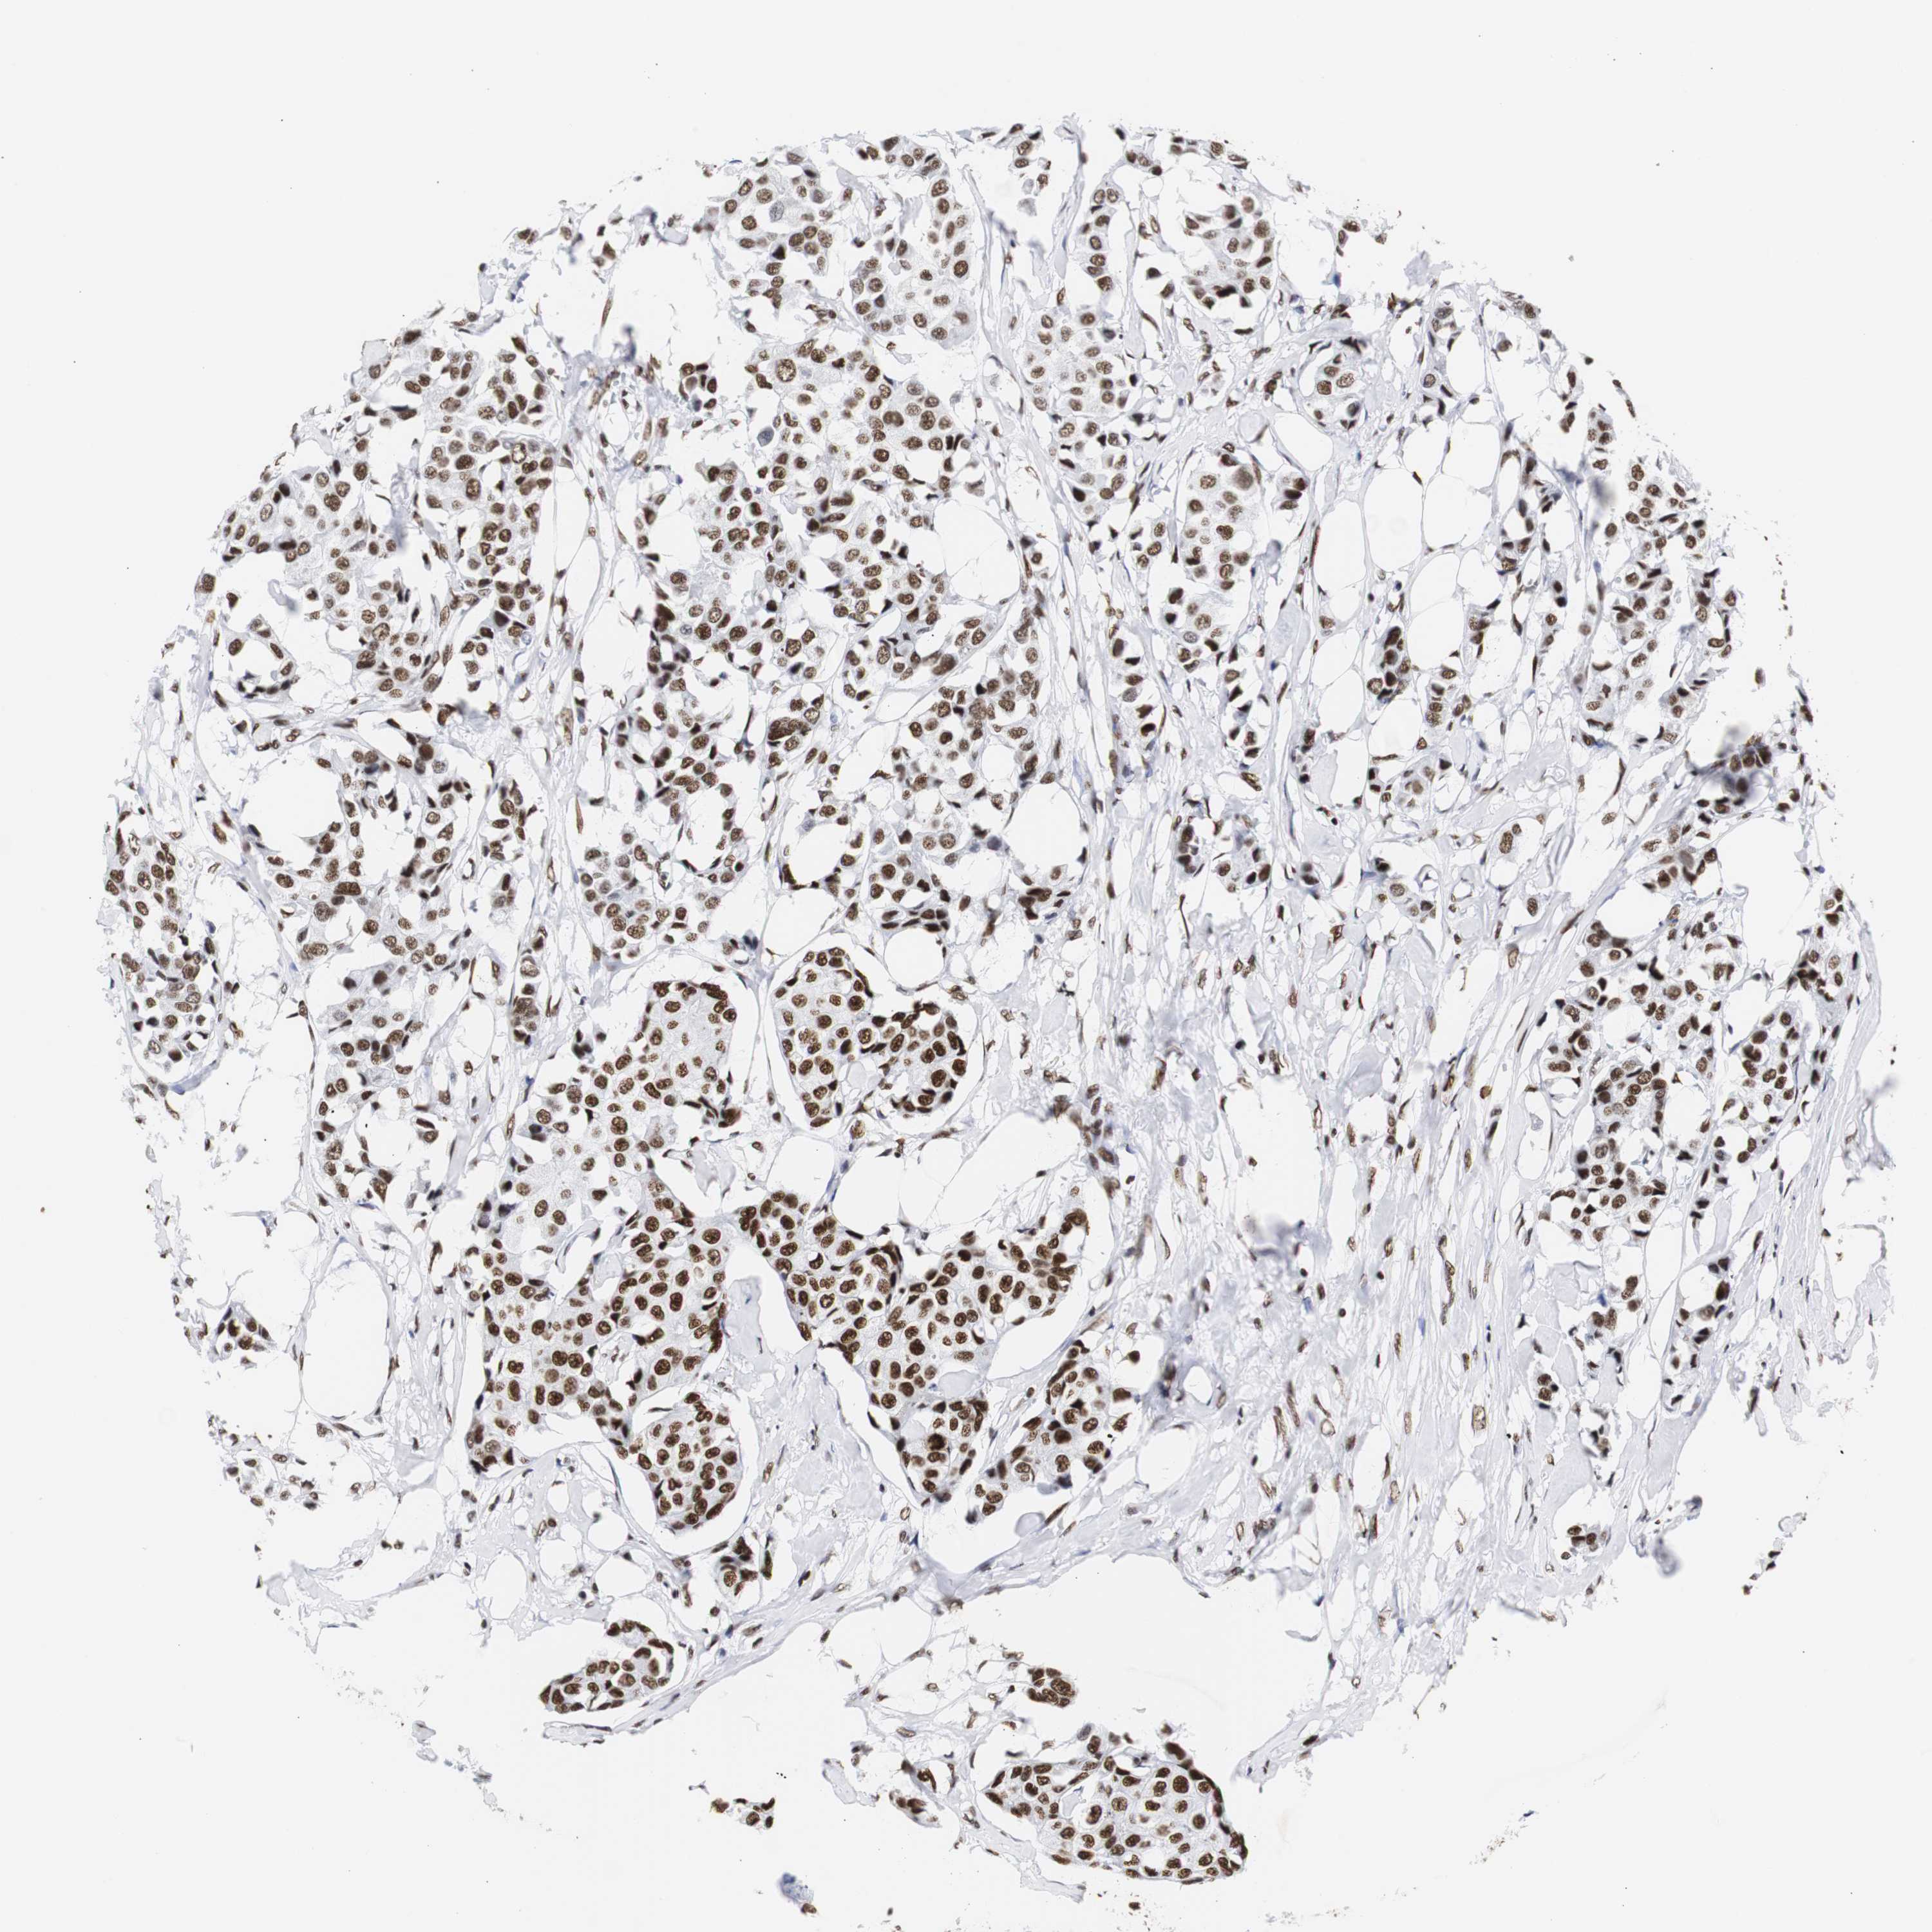

CANCER BREAST CANCER Show tissue menu

BRCA TCGA BRCA VALIDATION PROTEIN EXPRESSION